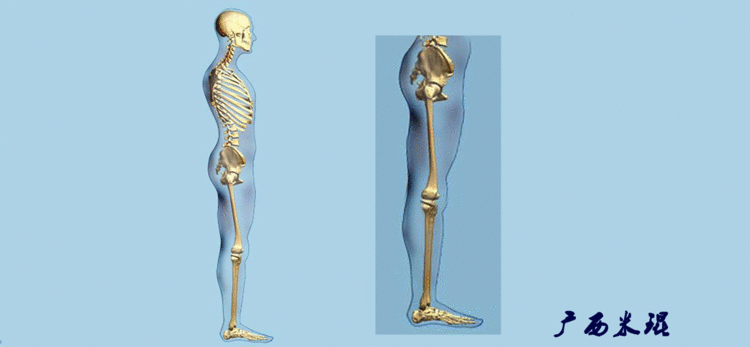

机械轴要分前后位及侧位,站立前后位(也就是冠状面)股骨头中心与踝关节中心的连线通过膝关节中心,这是下肢的机械轴线,也就是下肢力线,常说Mikulicz线。冠状面的力线评估在临床工作中最常用、最基础、最重要。

站立侧位(矢状面)股骨头中心与踝关节中心的连线也通过膝关节中心,这也是下肢的机械轴线,这也是下肢力线。

矢状面的下肢力线常常被医生忽视,其实它的改变也是膝关节疼痛的常见原因。

开始接触时可能我们对这些轴有点混乱,通过下面的这张图片就能清楚的了解下肢几个轴之间的关系。